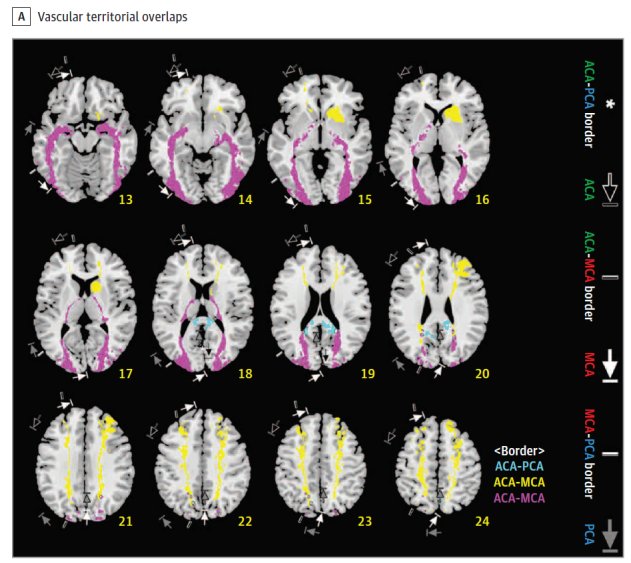

Cerebral vascular territories